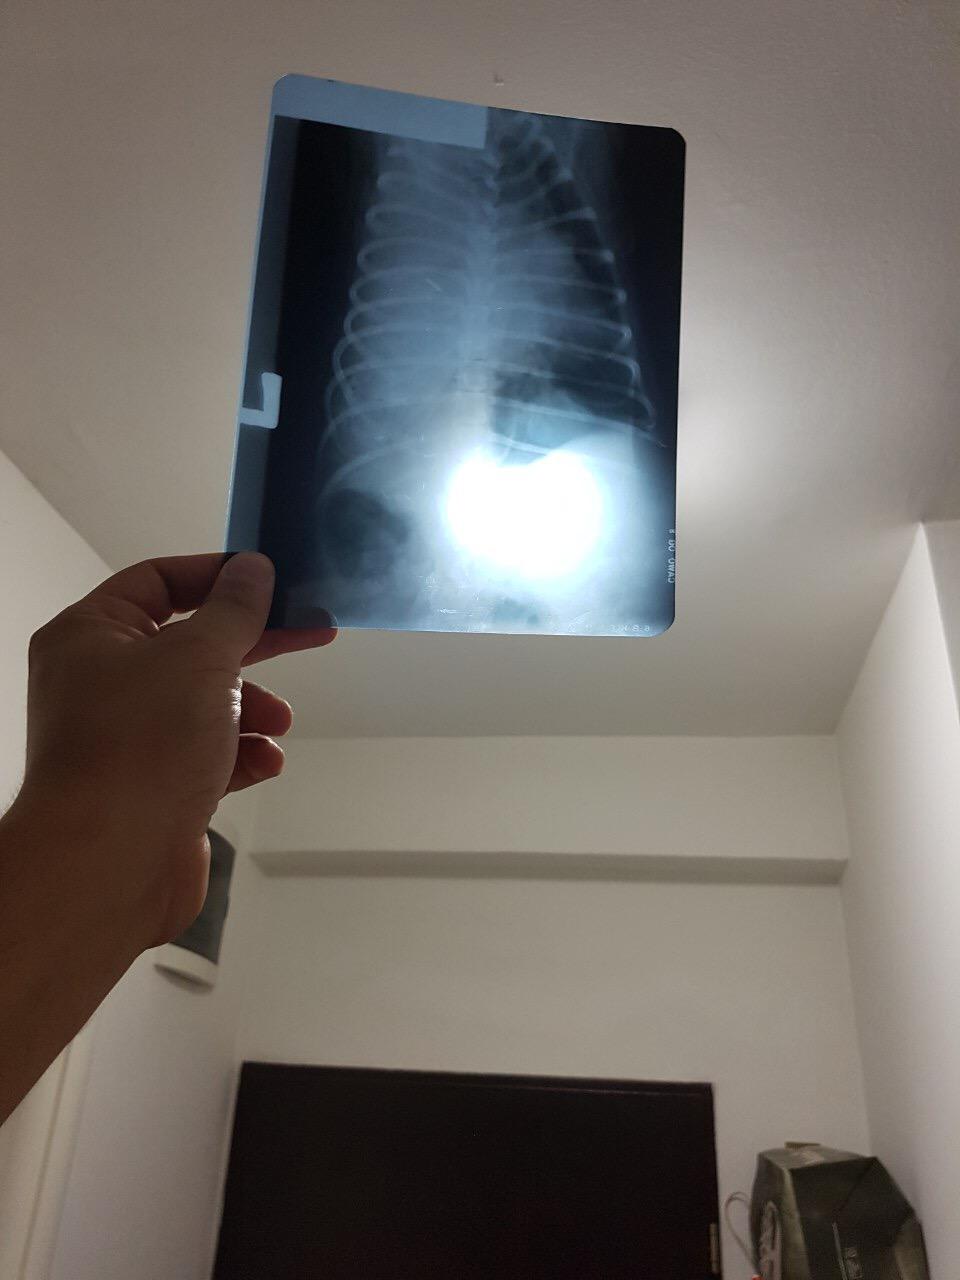

We are treating my pug (2,5 year old) from pneumonia one week with antibiotics and diuretics but today on xray showed suspected not defined tumor mass. What to do next to have the right diagnoze? Thank you

Hi and thanks for using Petco Pet Education Center, formerly Petcoach! Sorry to hear that Kan is having a problem. This could be tricky but the next step would be a CT scan or MRI Scan. Not sure if ultrasound would be helpful but maybe. A fine needle biopsy or aspirate of the mass or a surgical biopsy would hopefully be able to obtain some tissue from the mass to determine what it is. I cannot make out much on the xrays due to the quality over the internet. Possibilities of a mass always fall into some broad categories including an abscess (pus filled pocket from infection), a granuloma or collection of inflammatory cells), a seroma of fluid fulled sac, a hematoma or pocket of blood, or a tumor which could be benign (not cancer) or malignant (cancer). Kan is very young to have a tumor but it must be on the differential list. What else could it be? A very congested lung lobe from multiple things, a lung lobe torsion where a lobe of the lung turns on it's axis and is out of place, an area of calcification, etc. I hope this helps and I hope Kan does really well for you. I'm hoping for the best for you two.

I am sorry to hear that! It is hard to tell from the pictures, but I imagine your vet would want to re-check the x-rays and/or consider an ultrasound or visit to a specialist next. If he is on antibiotics and diuretics, I would imagine they are hoping for an improvement on the meds! I hope this helps and Kan is much better soon!